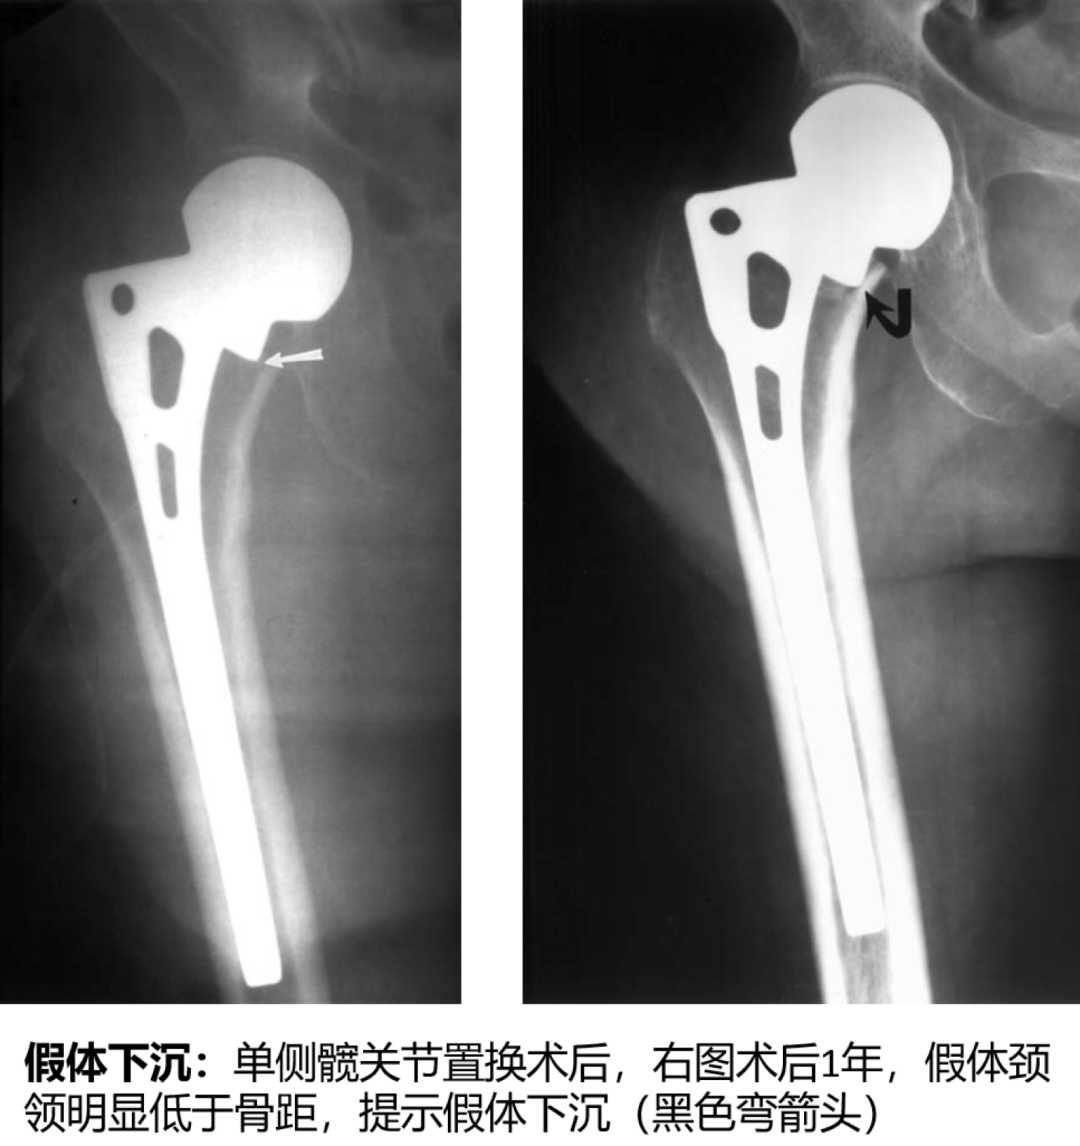

②股骨假体下沉/移位,髋臼假体移位/内陷;